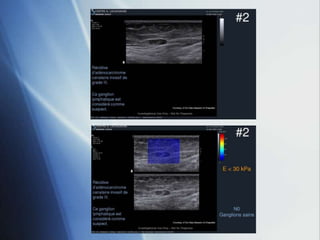

 Significant difference benign versus malign:

 Cancers: E = 170.1 ± 41.6 kPa

 Benign lesions: E = 53.5 ± 19.8 kPa

n= 36

Courtesy of Dr Anne Tardivon - Institut Curie - Paris